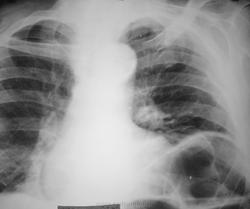

релаксація купола діафрагми зліва ??? чи грижа ???

релаксація купола діафрагми зліва ?

Хотелось бы увидеть снимок лучшего качества. Дополнительно левый боковой снимок. Возникает вопрос: А, что за инфильтрация справа?

Снимок с разворотом, на инфильтрацию не очень похоже. А релаксация - да, еще бы, так кишечник раздут.

Да, правый боковой тоже необходим. А что по поводу левой верхушки?

синдром хилаидити но слева

что касается верхушки снимок то не идеальный ,если жалобы есть сделать линейную томограмму . атак сближенность елементов легочного рисунка ,что в прочем и имеет место справа  еще в большей степени чем на верхшке слева .скорее всего это от давления .нижняя граница левой половины диафрагмы на уровне 8 ребра